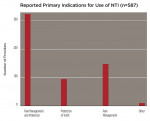

Fifty-six percent of responders (n = 322) used the device equally for headache and/or OFP management and tooth/restoration protection, while 26% (n = 147) used it primarily for pain management (Figure 4). Within these categories, 72% (n = 337) recommended using this particular appliance more than 80% of the time, whereas 87% (n = 409) used it for both short-term diagnosis/treatment and long-term therapy/prevention. When asked to categorize the anatomic pain profile of patients with NTI, 48% of treated patients had pain predominantly “above the cheeks” (migraine, tension, other primary headaches; temporalis pain); 34% were patients with pain “below the cheeks” (facial, tooth, pterygoid and masseter muscle, or neck pain); and 21% had pain predominately located in the TMJs. Four hundred and fourteen providers rated their perceived success with the use of the device. In pain-above-the-cheeks patients, practitioners rated their success with NTI treatment as 90% (n = 371). In patients with pain below the cheeks, 88% (n = 366) of cases were mostly successful, and in patients with joint pain, 74% (n = 306) of cases were mostly successful (Figure 5).